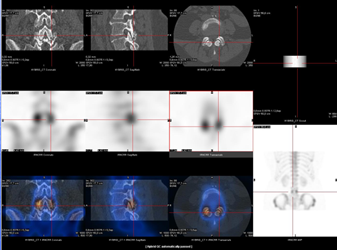

Une  grande partie des SPECT/CT osseux est réalisée lors de la recherche de métastases osseuses surtout dans le cadre des néoplasies prostatique ou mammaire (1,2).

Le rachis et le bassin sont les localisations les plus fréquentes de métastases osseuses.

La reconnaissance de ces métastases est cruciale. Or, ces régions anatomiques sont souvent le siège de pathologies coexistantes, telles qu’une maladie dégénérative ou des fractures, qui peuvent rendre difficile le diagnostic différentiel entre pathologie bénigne ou maligne. Dans ces cas, la réalisation d’un SPECT/CT apporte une précision diagnostique améliorée en corrélant les imageries fonctionnelle et anatomique. (fig. 2)

Figure 2 - A gauche: lésion métastatique osseuse - A droite : arthrose.